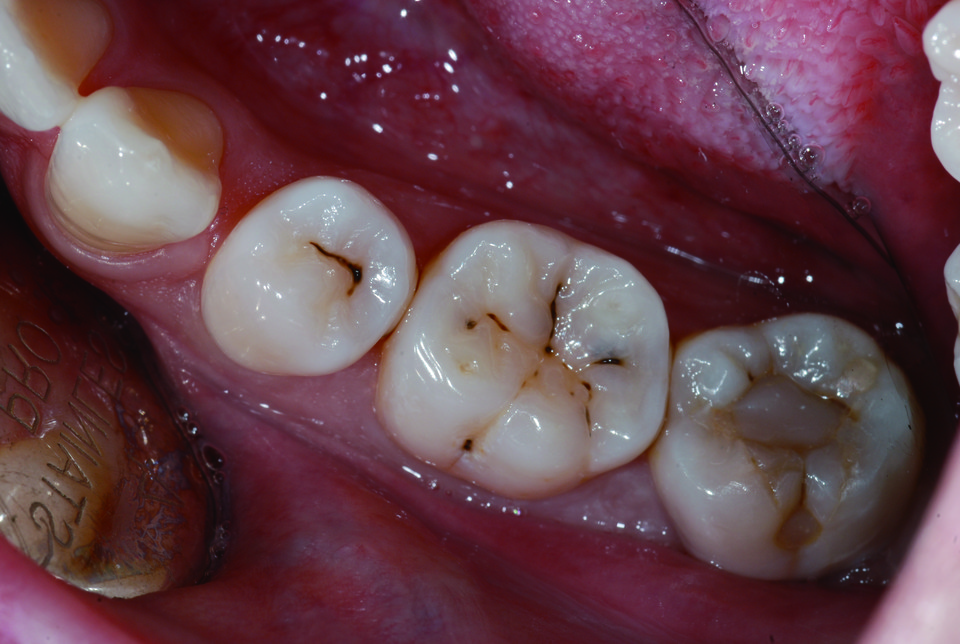

또 High Flow는 base 외에 교정 retainer 의 부착, 실란트 등 치료에도 활용 가능합니다. 방사선 불투과성이 높기 때문에 방사선상에서 우식과 구분이 쉽게 가능하며 2.0 & 0.7µm 와 20nm의 다양한 크기의 필러를 함유함으로써 내마모도에도 강한 모습을 보이기 때문에 구치부 수복에도 유용합니다. (그림7~11)